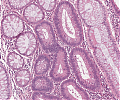

A69 Tubuläres Adenom (Kolon)

Nebeneinander normaler Kolondrüsen und adenomatöser Drüsen.

A69 Tubuläres Adenom (Kolon)

Tubuläre Drüsenbildung mit geringen Epithelatypien und einzelnen noch erhaltenen Becherzellen.